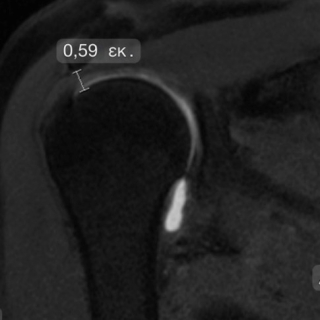

- Σύνδρομο πρόσκρουσης – ο υπερακανθιος “προσκρούει” κάτω από το ακρώμιο. Το φαινόμενο αυτό είναι συχνό όταν η απόσταση μεταξύ ακρωμίου και βραχιονίου είναι μικρότερη των 7,5-8 mm

Μειωμένη ακρωμιοβραχιόνια απόσταση